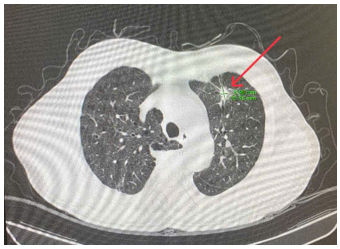

Hình 1. Khối kích thước 17x19 mm, bờ tua gai, ngấm thuốc cản quang. Cả 2 trường phổi có giãn phế nang lan toả ở thuỳ trên phổi trái

Hình 6. Nốt đặc kích thước 16x10mm (nhỏ hơn phim chụp tháng 7/2024) bờ tua gai, ngấm thuốc không đồng nhất sau tiêm ở thuỳ trên phổi trái